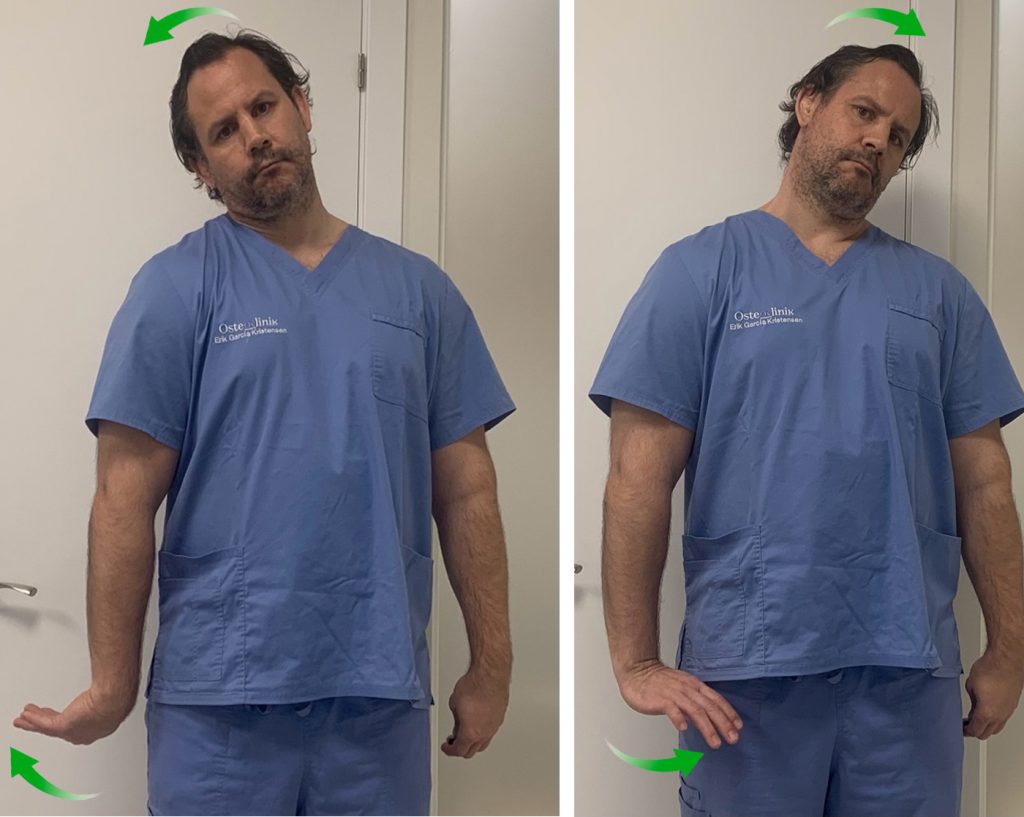

3. Nervio Cubital

Vamos a realizar, primero, una puesta en tensión y estiramiento del nervio para después pasar a una movilización.

Partimos de una posición erguida de pie o sentado.

Con el pulgar y el índice hacemos “pinza” describiendo un pequeño círculo.

Vamos a realizar una flexión del hombro elevando el codo, a la vez que hacemos flexión del codo y flexión dorsal de la muñeca como si quisiéramos colocarnos unos “anteojos”.

Muy probablemente no consigamos llegar hasta colocar la palma de la mano en nuestra cara. No importa, llegamos lo más cerca que podamos.

De esta manera estamos poniendo en tensión el nervio cubital y podemos sentir la sensación de tensión y cierto hormigueo en el brazo y la mano.

Para movilizar el nervio, vamos a repetir esta secuencia bajando el codo y estirándolo y haciendo flexión palmar de la muñeca. Y volviendo de nuevo a la posición de estiramiento.